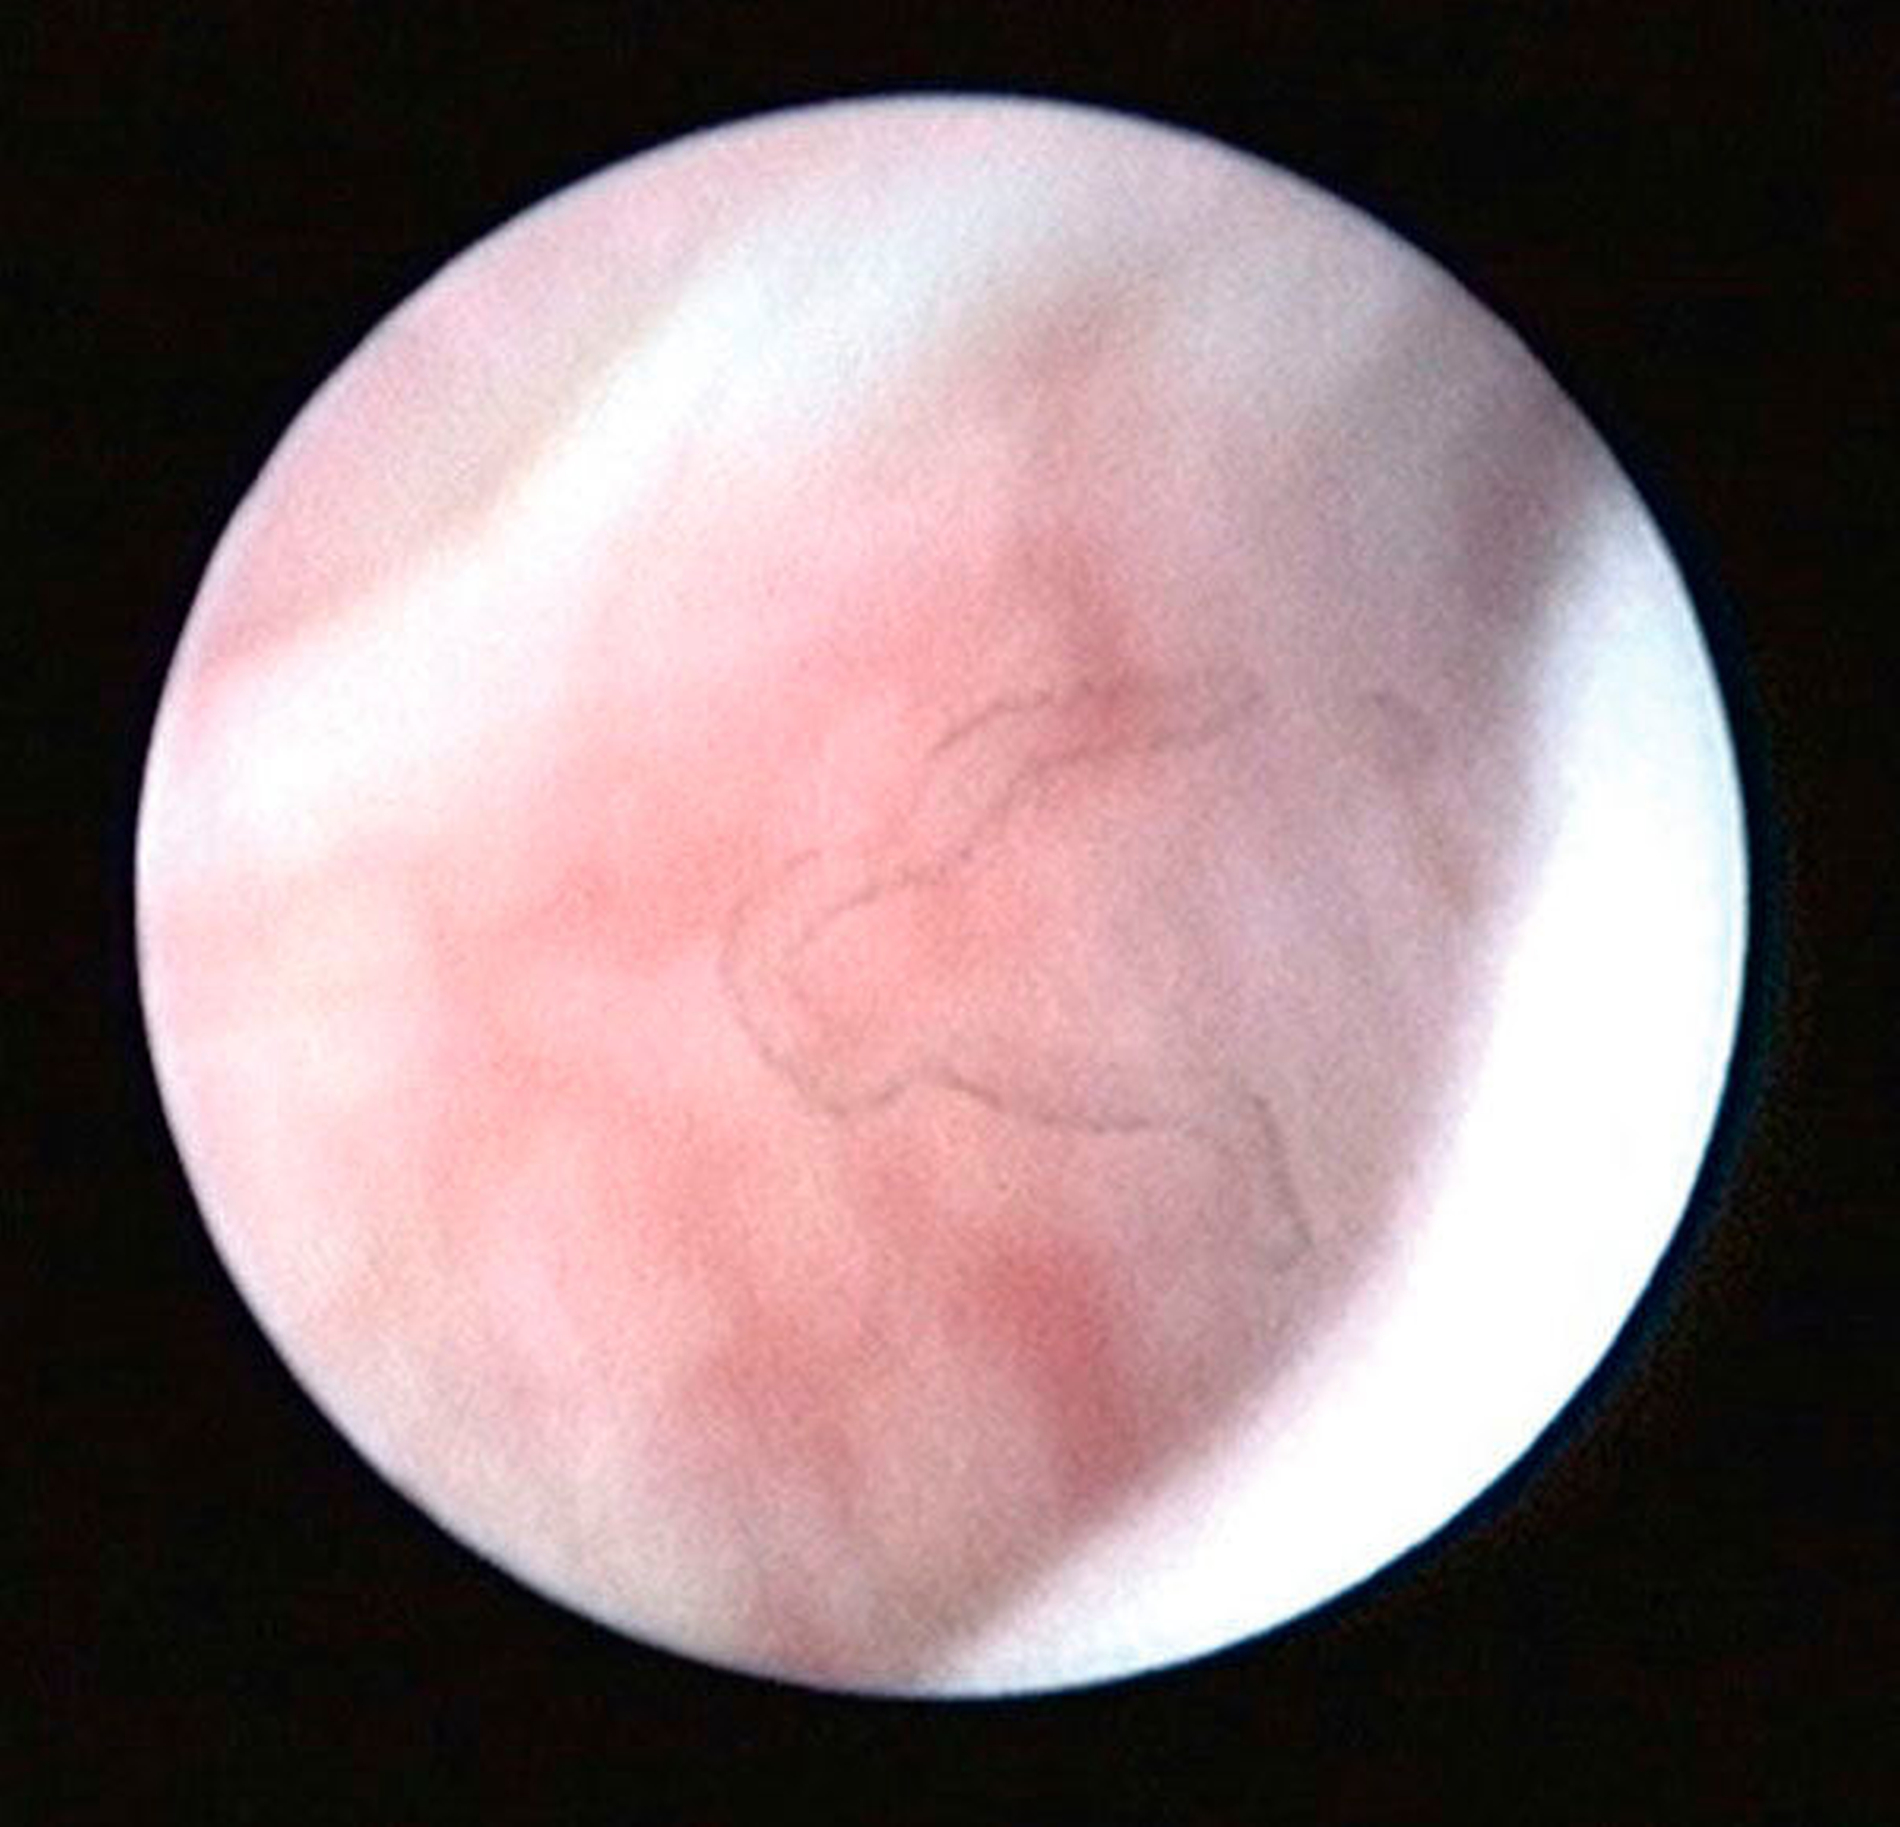

Die Kiefergelenksdestruktion wird als Ergebnis eines katabolen Prozesses verstanden, der die regenerativen Fähigkeiten des Gelenks überlagert und unter anderem durch eine kaskadenartige Aktivierung von Zytokinen vermittelt wird. Dabei kommt es neben einem Verstärkungseffekt durch die Synovial- und Gefäßproliferation zu einer Aktivierung von Osteoblasten. Zytokin-aktivierte Osteoblasten fördern die Rekrutierung und Aktivität von Osteoklasten, diese sezernieren wiederum Enzyme wie beispielsweise Matrix-Metalloproteasen (MMPs), die für den Abbau der extrazellulären Matrix (Hydroxylapatit und Kollagen) des Gelenks verantwortlich sind [Gunson et al., 2011; Zhang et al., 2016; Wang et al., 2012: Ge et al., 2011]. Die Schädigung des Gelenkknorpels wird dabei als „Chondromalazie“ bezeichnet und bei der arthroskopischen Diagnostik je nach Schweregrad im Stadium der Erweichung (Stadium 1), Furchung (Stadium 2), Fibrillation beziehungsweise Fransenbildung (Stadium 3) oder mit subchondraler Knochenexposition (Stadium 4) vorgefunden (Abbildungen 1 bis 3) [Quinn, 1989; Thomas et al., 1991].

Arthroskopisch existieren verschiedene Klassifikationen der Synoviitis, die im Wesentlichen das Ausmaß der beobachteten Gefäßproliferation und Hyperämie berücksichtigt (Abbildungen 4 bis 6) [Mc Cain et al., 1989; Gynther et al.,1994].

Die Kiefergelenksarthroskopie bietet bei gleichzeitiger Lavage eine überragende visuelle Diagnostik des oberen Gelenkraums (Abbildungen 1 bis 7, 13 und 14).

Zur Planung eines arthroskopischen Eingriffs am Kiefergelenk sollte ein möglichst aktuelles MRT der Kiefergelenke vorliegen, sofern hierfür keine Kontraindikationen bestehen. Dabei ist zu beachten, dass radioogisch diagnostizierte Pathologien durch die MRT nicht zwingend voraussetzend für eine Kiefergelenksarthroskopie sind. Bei Patienten mit symptomatischen Kiefergelenkschmerzen, aber radiologisch okkulten Kiefergelenksentzündungen ist die Kiefergelenksarthroskopie bislang immer noch das einzig relevante Verfahren zur Sicherung der Diagnose (Abbildungen 4 bis 6).